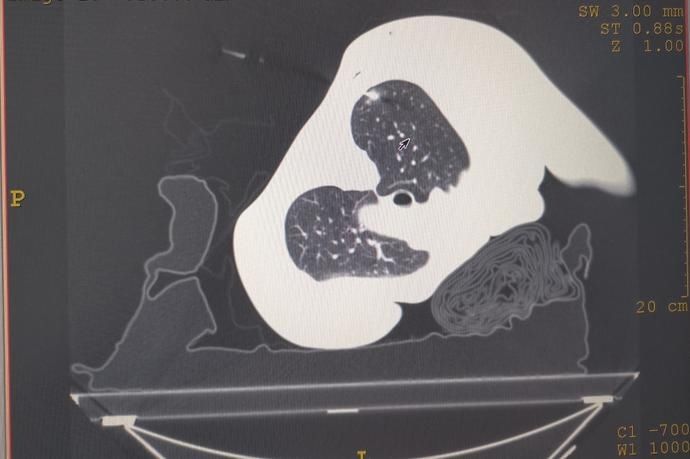

72岁孙大娘(化名)

因乳腺癌术后常规检查行胸部CT发现右肺上叶及下叶各有一个磨玻璃结节,大小约8.6mm×7.7mm

由孙建男副院长领衔的肺结节MDT专家团队对患者肺小结节进行了综合评估,根据胸部CT上肺结节的影像特征(>8mm磨玻璃结节),结合患者有乳腺癌手术史,认为此患者肺小结节为早期肺癌可能性大,建议患者手术治疗